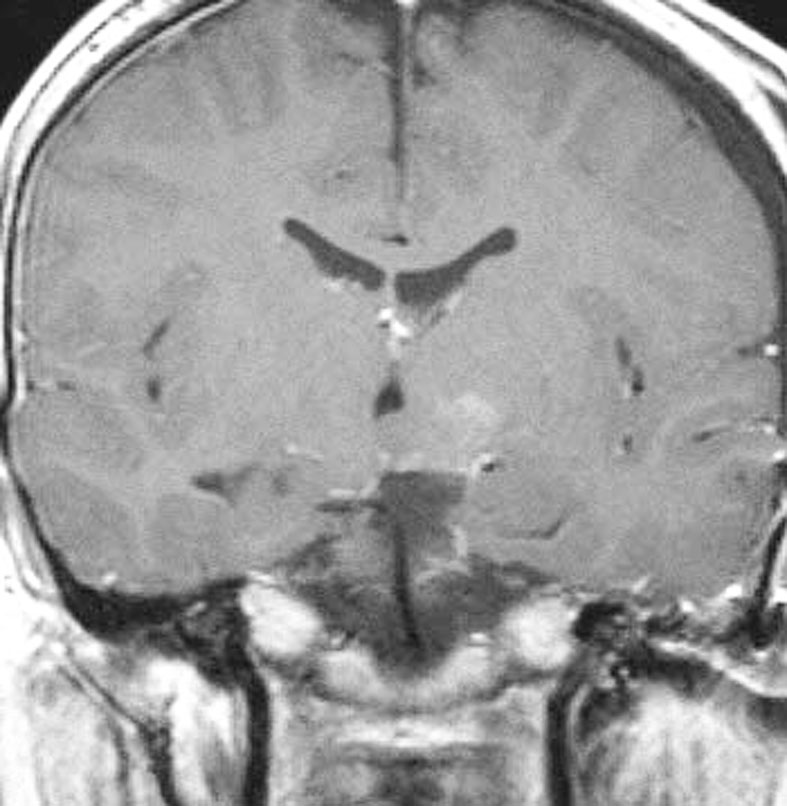

幼児期に思春期早発で発症

思春期早発で発症した幼児の視床下部過誤腫

視神経交叉の後方,乳頭体の前からぶら下がるようにしてあります

典型的な有茎状タイプです